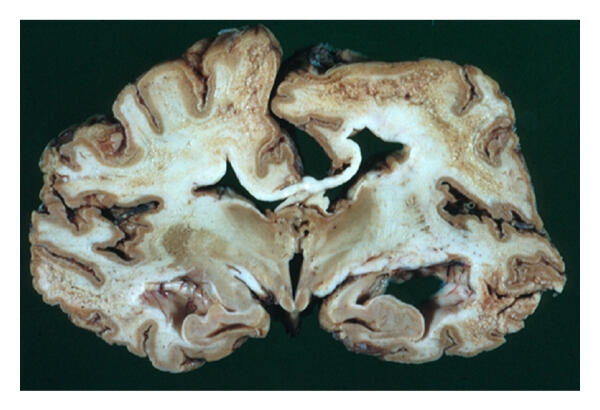

Bovine spongiform encephalopathy (BSE) and Creutzfeldt-Jakob disease (CJD) belong to a group of progressively degenerative neurological diseases known as transmissible spongiform encephalopathies (TSEs). TSE diseases are characterized by long incubation periods ranging from several months to several years.

There is no visible evidence of the disease during the incubation period. In 2008, the FDA published a regulation banning tissues that have the highest risk of transporting the agent that causes BSE in animal feed. These high-risk bovine materials are the brain and spinal cord of cattle from 30 months of age. The 2008 rule also prohibits the use of whole carcasses of livestock that have not been screened and transmitted for human consumption, unless the livestock are less than 30 months old or the brain and spinal cord have been removed. A BSE free certificate issued by a cosmetics association such as ACMA explains that the listed products do not contain prohibited materials and that the manufacturing process and packaging are equally pollution-free.